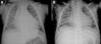

On admission he was apyretic, with pulse 190 bpm, respiratory rate 70–80 breaths per minute and oxygen saturation 95% in room air. His body weight was 6 kg (50th percentile). Physical examination revealed an infant of normal appearance but irritable and in respiratory distress. He was tachycardic, with an S3/S4 gallop rhythm. There were moist rales in the lung fields and chest wall retraction. The abdominal exam revealed hepatomegaly. The extremities displayed cyanosis and poor perfusion, with no edema. The chest X-ray showed cardiomegaly (cardiothoracic ratio 0.8) with pulmonary congestion (Figure 1A). The echocardiogram revealed a markedly enlarged left ventricular (LV) cavity with hypokinetic ventricular wall motion. LV end-diastolic diameter was 45 mm, LV end-systolic diameter was 40 mm, and fractional shortening (FS) was 5%, with no structural abnormalities (Figure 2). Electrocardiography showed sinus tachycardia (heart rate 190 bpm), LV hypertrophy and normal QTc.

Decreased serum calcium levels remained an issue while in the intensive care unit, requiring calcium boluses and drips to improve levels, which led us to study the patient's phosphorus–calcium metabolism. Hormone levels that were changed included elevated parathyroid hormone (231.8 pg/ml, reference value: 12–80 pg/ml), decreased 25-hydroxyvitamin D (5.94 ng/ml, reference value 11–70 ng/ml) and decreased 1,25 (OH)2 vitamin D3 (18.57 pg/ml, reference value: 20.2–46.2 pg/ml). There were no metabolic disorders on amino acid and organic acid tests. Calcium and vitamin D deficiency was confirmed and replacement with calcium and alfacalcidol (0.05 μg/kg/day) was started. As the levels of serum calcium increased to normal, the patient showed rapid recovery of cardiac function, normalization of LV dimensions and function on echocardiogram (Figure 3) and reduction of cardiomegaly on chest X-ray (Figure 1B). As the infant improved clinically, he was weaned to oral captopril, furosemide, spironolactone and digoxin. He was discharged on the 25th hospital day and followed in the outpatient clinic, with calcium gluconate and calcitriol replacement.